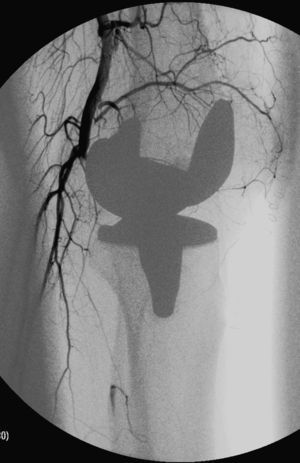

Casos clínicosCaso 1Paciente varón de 55 años con dislipemia como único antecedente médico-quirúrgico de interés. Fue intervenido con realización de artroplastia total de rodilla bajo bloqueo locorregional. Durante el postoperatorio inmediato el paciente refirió dolor intenso en el pie izquierdo acompañado de palidez y frialdad. A la exploración física presentaba ausencia de pulsos a nivel poplíteo y distal en el miembro afecto. La motilidad se mantenía conservada y presentaba alteración de la sensibilidad, aunque poco valorable por persistencia del bloqueo regional. Ante el cuadro de isquemia aguda se realizó arteriografía intraoperatoria, evidenciando trombosis de la segunda porción de la arteria poplítea con permeabilidad de la tercera porción y arterias distales (fig. 1). Ante dichos hallazgos se practicó trombectomía desde la tercera porción de la arteria poplítea proximalmente y a los troncos distales, con posterior by-pass entre la primera y la tercera porción de la misma con la vena safena interna invertida ipsilateral, por la recuperación de un flujo inadecuado tras la trombectomía a nivel poplíteo. El paciente recuperó los pulsos distales sin sufrir secuelas, y al año se encontraba asintomático con by-pass permeable según la eco-doppler y pulsos distales palpables.

Caso 3Paciente varón de 63 años de edad con antecedentes de hipertensión arterial y síndrome depresivo que presentó durante el postoperatorio inmediato, tras artroplastia total de rodilla, un episodio de edema en la pierna y el pie con dolor y frialdad. En la exploración física presentaba importante edema, enlentecimiento del relleno capilar y ausencia de pulsos distales, con sensibilidad y motilidad conservadas. Se realizó arteriografía que evidenciaba la existencia de una estenosis corta y excéntrica en la segunda porción de la arteria poplítea, compatible con disección intimal, y permeabilidad a nivel de los troncos distales (fig. 2). Se realizó tratamiento conservador con anticoagulación sistémica (HBPM 1mg/kg/12h) y seguimiento clínico y ecográfico. A los 6 meses el paciente estaba asintomático, con presencia de pulso pedio y permeabilidad poplítea en la eco-doppler, por lo que se decidió retirar la anticoagulación y continuar con antiagregación de forma indefinida.